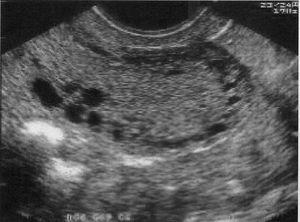

El diagnóstico definitivo se lleva a cabo en el estudio histológico de las piezas de histerectomía (fig. 1), aunque se está realizando una tentativa seria de diagnóstico preoperatorio mediante las biopsias miometriales y el diagnóstico por la imagen (ecografía transvaginal y resonancia magnética). A pesar de que la adenomiosis se presenta en el 5-70% de las pacientes y que se asocia hasta en un 80% de los casos con miomas, los informes de ultrasonografía raramente informan de adenomiosis. En este sentido, el rol de las imágenes en la evaluación de estas pacientes permitirá establecer una aproximación diagnóstica, determinar la profundidad y la extensión de la penetración del miometrio y monitorizar la evolución de las pacientes que reciban terapia conservadora.

Fig. 1. Adenomiosis. Componente glandular endometrial en el seno de miometrio normal.